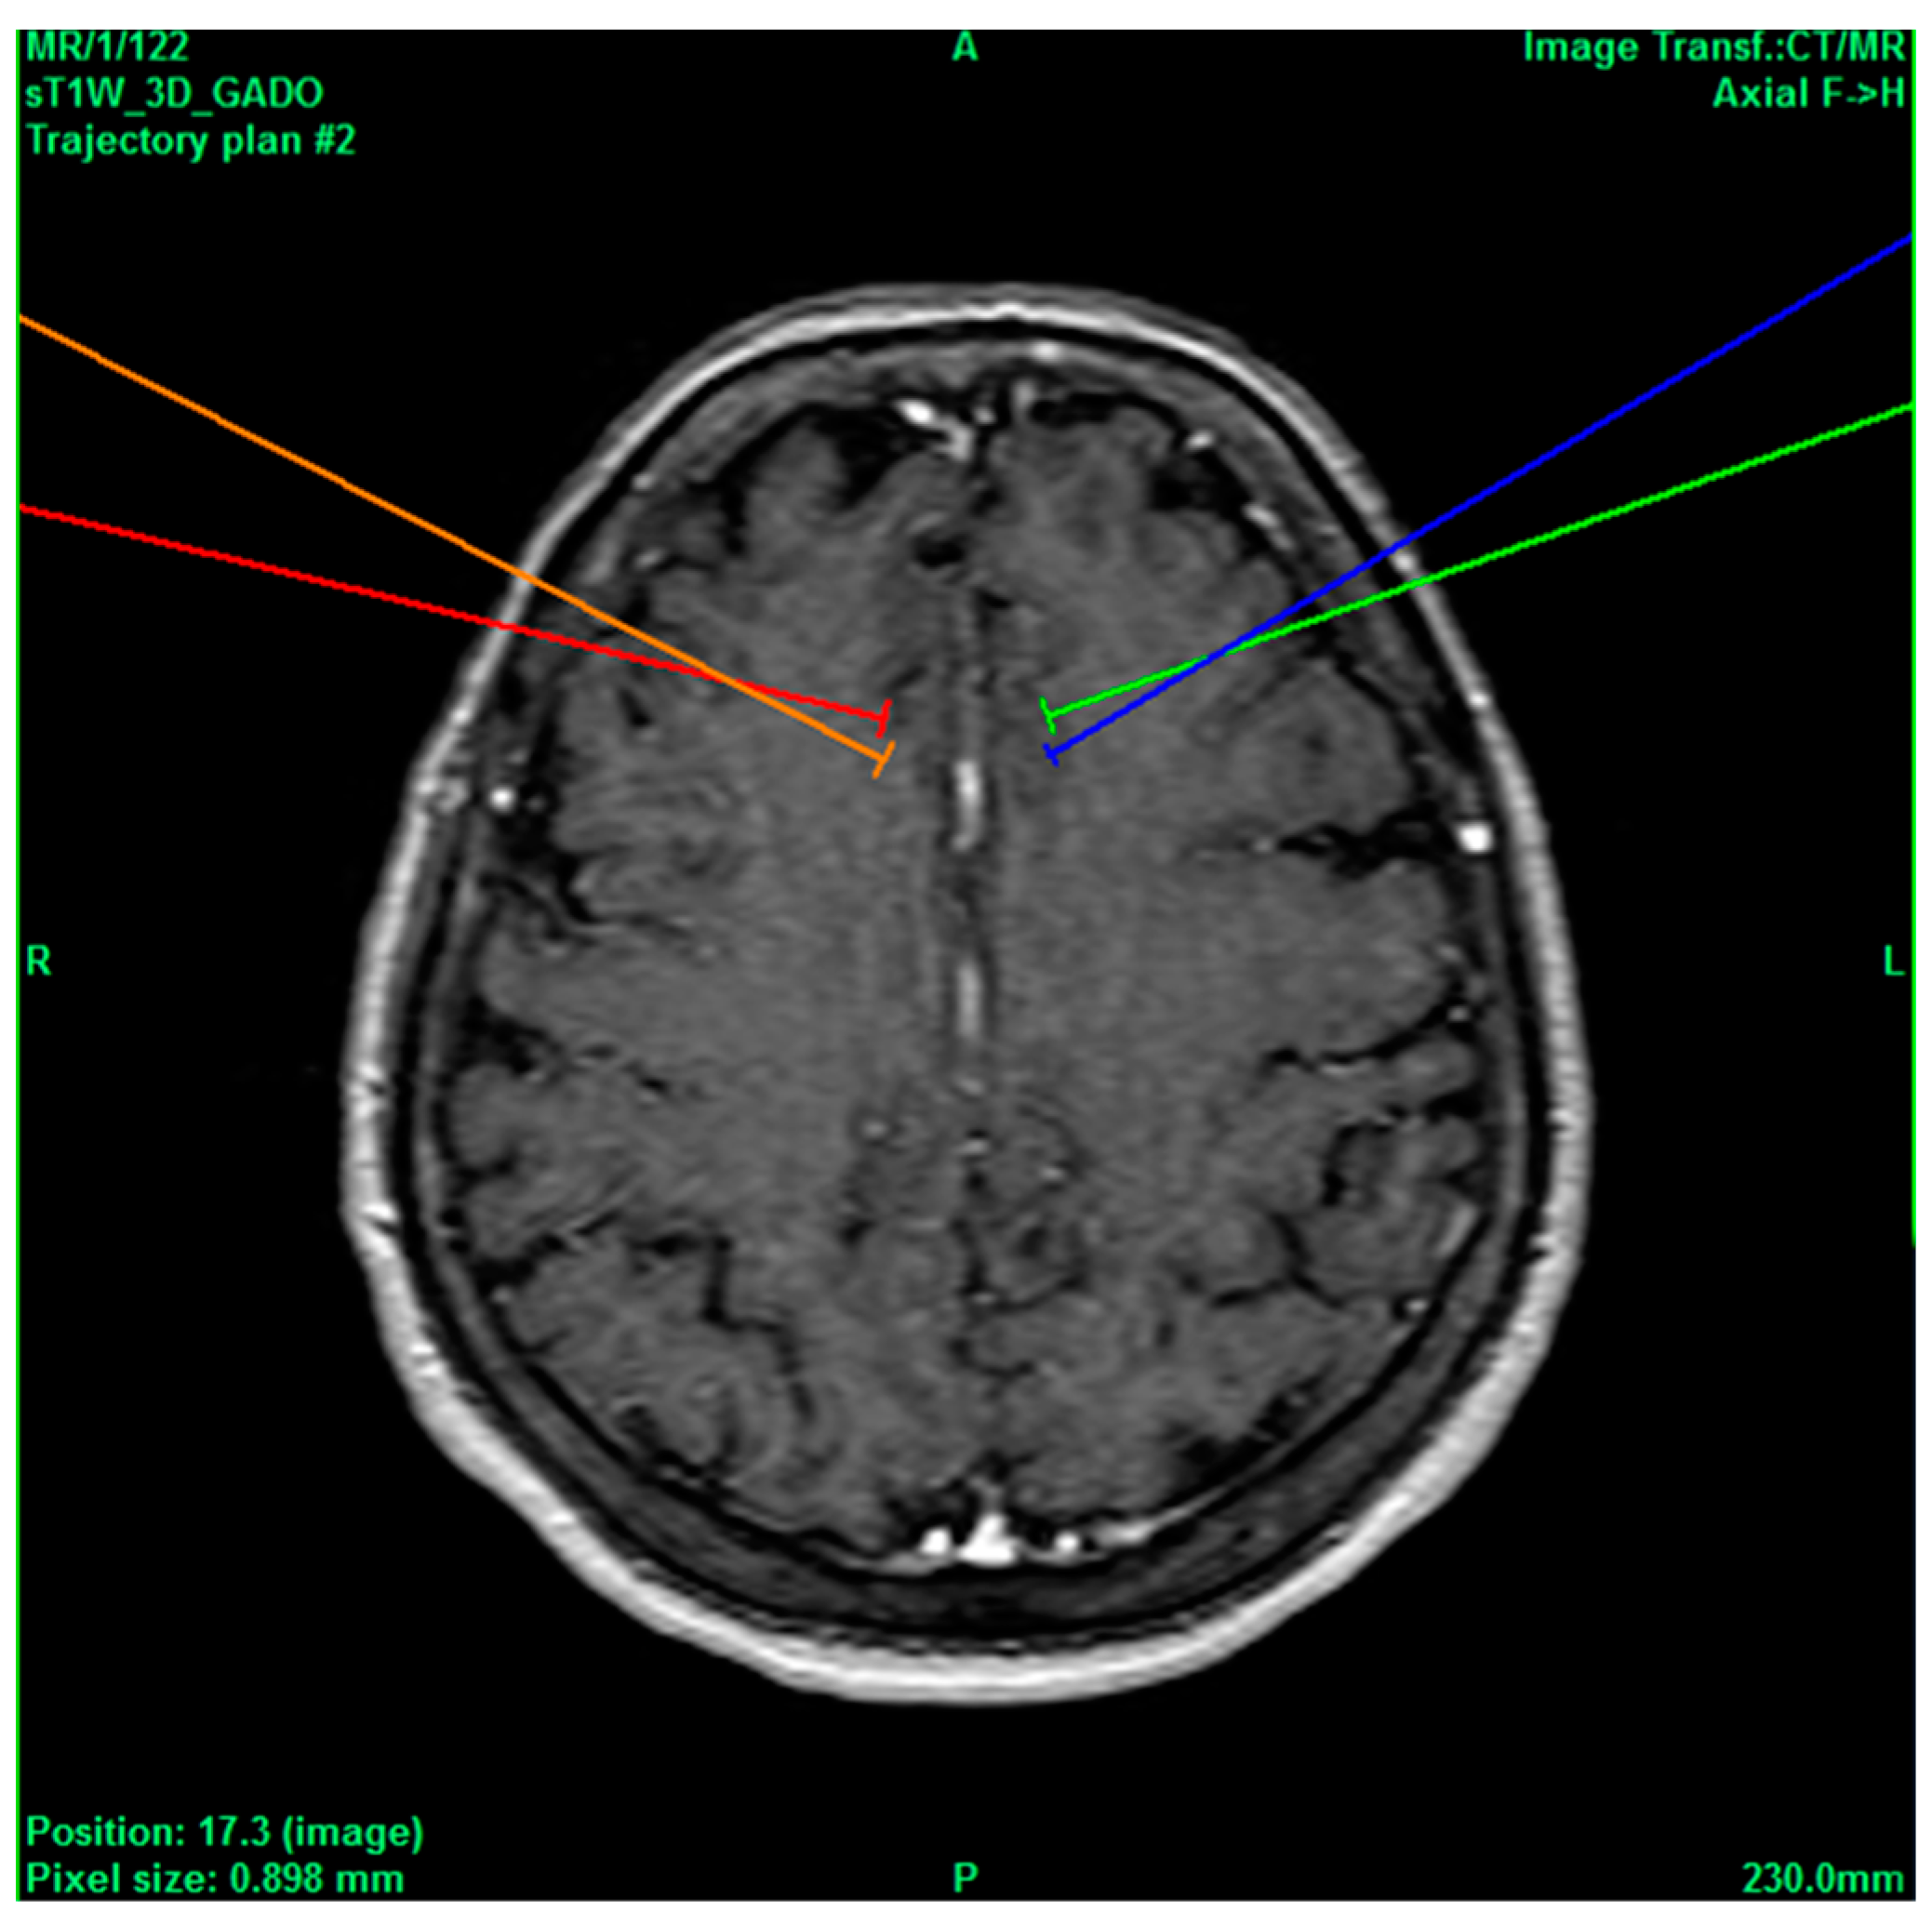

Figure 2.

Bilateral projection of cross-sectional cingulotomy from patient 1.